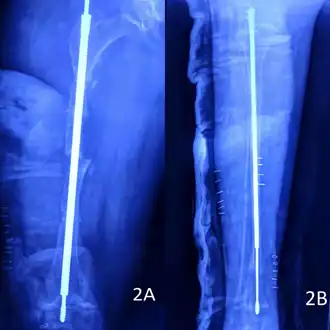

The tip of a modern Fassier–Duval telescoping intramedullary rod, manufactured by Pega Medical for use in osteogenesis imperfecta.[114]

The right femur (2A) and tibia (2B) of a 10-year-old girl immediately after her rodding surgery, which involved implantation of the same type of telescoping intramedullary rod photographed at left.[114] Note the bone fragmentation, an important step in the procedure, clearly visible on the X-ray of the femur.

Metal rods can be surgically inserted in the long bones to improve strength, a procedure developed by Harold A. Sofield when he was Chief of Staff at Chicago's Shriners Hospitals for Children, a hospital that offers orthopedic care and surgery to children regardless of their family's ability to pay.[115] Large numbers of children with OI came to Shriners, and Sofield experimented with various methods to strengthen their bones.[116] In 1959, with Edward A. Millar [sic], Sofield wrote a seminal article describing a three-part surgery that seemed radical at the time: precisely breaking the bones ("fragmentation"), putting the resulting bone fragments in a straight line ("realignment"), then placing metal rods into the intramedullary canals of the long bones to stabilize and strengthen them ("rod fixation").[117] His treatment proved useful for increasing the mobility of people with OI, and it has been adopted throughout the world—it became standard surgical treatment for severe OI by 1979, in which year David Sillence found that ≈23 of the patients he surveyed with OI type III had undergone at least one rodding surgery.[42]: 108

In those with type III OI who had undergone rodding surgery, 79.5% had the femurs and tibias of both legs rodded.[25]: Table I  The most common form of rods used are intramedullary (IM) rods, some of which, such as the Fassier–Duval IM rod, are telescoping, meaning that they are designed to grow as the child grows, in an attempt to avoid the necessity of revision surgeries.[118] Telescoping IM rods are widely used,[119] and the common Fassier–Duval IM rod is designed to be used to rod the femur, tibia, and humerus.[120]: 1  The surgery involves breaking the long bones in between one and three (or more)[119]: Figure 4  places, then fixing the rod alongside the bone to keep it straight.[120]: 11